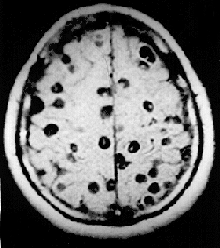

Magnetic resonance image of a patient with neurocysticercosis demonstrating multiple cysticerci of the pork tapeworm Taenia solium within the brain

Cestodes (tapeworms) and digeneans (flukes) cause diseases in humans and their livestock, whilst monogeneans can cause serious losses of stocks in fish farms.[45] Schistosomiasis, also known as bilharzia or snail fever, is the second-most devastating parasitic disease in tropical countries, behind malaria. The Carter Center estimated 200 million people in 74 countries are infected with the disease, and half the victims live in Africa. The condition has a low mortality rate, but usually presents as a chronic illness that can damage internal organs. It can impair the growth and cognitive development of children, increasing the risk of bladder cancer in adults. The disease is caused by several flukes of the genus Schistosoma, which can bore through human skin; those most at risk use infected bodies of water for recreation or laundry.[28]

In 2000, an estimated 45 million people were infected with the beef tapeworm Taenia saginata and 3 million with the pork tapeworm Taenia solium.[45] Infection of the digestive system by adult tapeworms causes abdominal symptoms that, whilst unpleasant, are seldom disabling or life-threatening.[46][47] However, neurocysticercosis resulting from penetration of T. solium larvae into the central nervous system is the major cause of acquired epilepsy worldwide.[48] In 2000, about 39 million people were infected with trematodes (flukes) that naturally parasitize fish and crustaceans, but can pass to humans who eat raw or lightly cooked seafood. Infection of humans by the broad fish tapeworm Diphyllobothrium latum occasionally causes vitamin B12 deficiency and, in severe cases, megaloblastic anemia.[45]